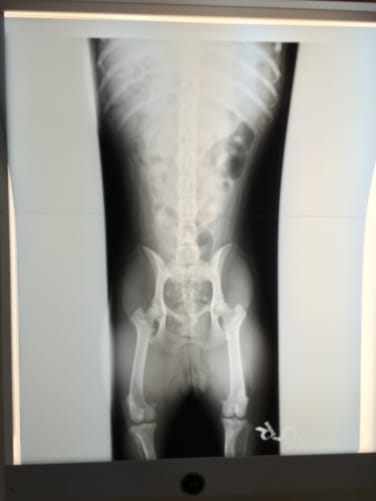

Nach diversen Untersuchungen stellte sich heraus, dass Sora eine gerochene Hüfte hat. Bei diesem komplizierten Bruch steht der Verdacht auf ein künstliches Hüftgelenk immer noch im Raum. Ausserdem wurde durch den Aufprall das Auge und die Hornhaut stark verletzt. Sie fragten uns ob wir die Behandlung durchführen möchten, ich bejahte sofort, da uns unsere Maus seit dem ersten Tag begleitet.